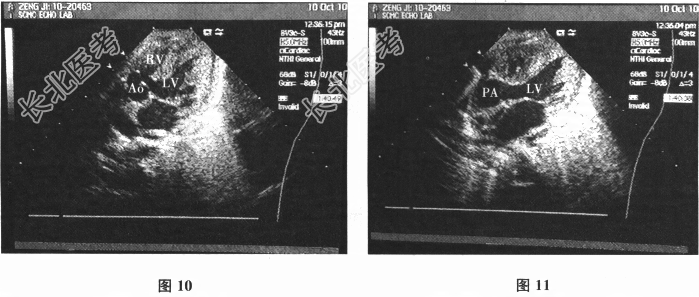

- 多项选择题3.超声心动图(胸骨旁四腔切面,图10、图11): 心脏位置正常,心房正位、心室正位。房室连接一致, 心室大动脉连接不一致,主动脉骑跨, 大部分发自左心室,位于左前, 主动脉瓣开放活动可,瓣环1.3cm; 肺动脉发自左心室,位于右后, 肺动脉瓣叶稍增厚,回声稍强, 开放活动受限,瓣环0.94cm, 流速2.7m/s,左肺动脉1.0cm, 右肺动脉0.99cm。RVDD1.1cm,LVDD2.8cm, 二尖瓣环1.5cm,轻度反流; 三尖瓣环0.93cm,轻微反流。左位主动脉弓, 降主动脉流速1.0m/s。该患者诊断应包括( )

A、右心室双出口

B、左心室双出口

C、室间隔缺损,肺动脉瓣下

D、室间隔缺损,主动脉瓣下

E、肺动脉高压

F、右心室发育不良

G、主动脉缩窄

关注下方微信公众号,搜题查看答案